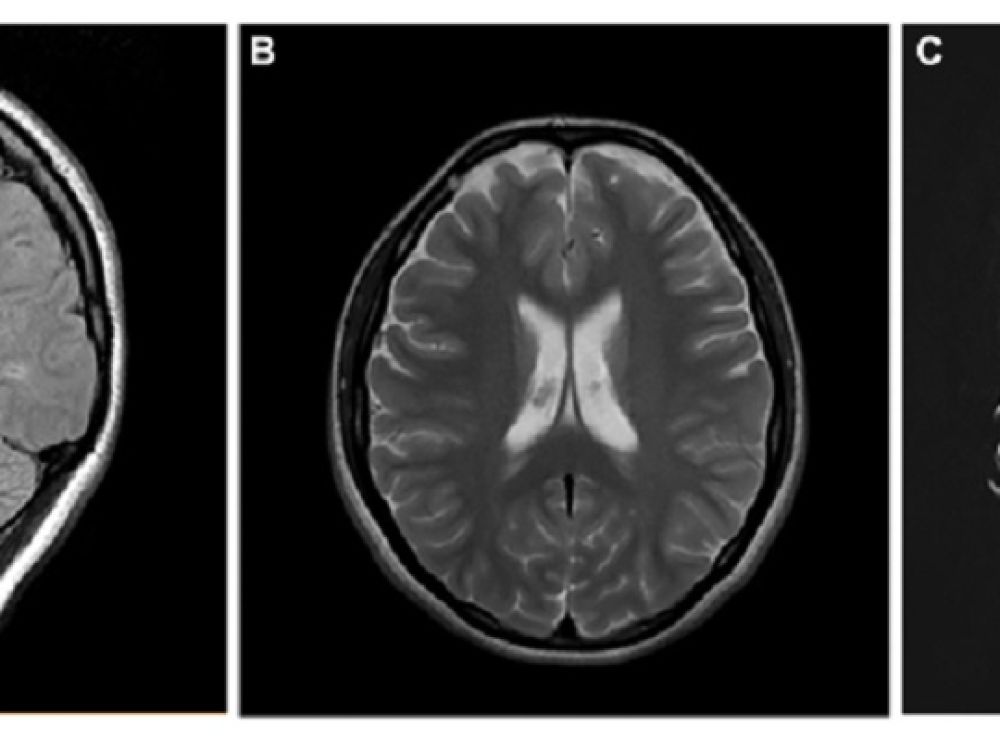

Scans of the brain

MISSOULA – An opinion paper published by University of Montana professor Lilian Calderón-Garcidueñas MD, PhD identifies air pollution risk exposures and the development of Alzheimer’s and Parkinson’s diseases, frontotemporal lobar degeneration (FTLD) and amyotrophic lateral sclerosis (ALS) in exposed populations.

Dr. Calderón-Garcidueñas comments that with the new PM 2.5 standard de facto, millions of US residents will be living in PM2.5 non-attainment regions and in addition, society must deal with the tinniest particles, so called ultrafine particulate matter UFPM and industrial nanoparticles NPs exposures because their ability to cross all biological barriers, reaching the brain and other critical organs (i.e., the heart). This fraction of PM2.5 has strong neurodegenerative/neurobehavioral/brain structural associations. The early development and progression of Alzheimer’s and Parkinson’s diseases and FTLD and ALS already killing thousands of Americans - should raise red flags about the need to understand this serious potential UFPM and NPs risk to urban and rural US populations.